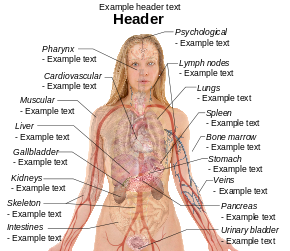

English: Main symptoms of different variants and stages of tuberculosis (See Wikipedia:Tuberculosis), with many symptoms overlapping with other variants, while others are more (but not entirely) specific for certain variants. Multiple variants may be present simultaneously.

Pulmonary tuberculosis symptoms

Extrapulmonary tuberculosis symptoms